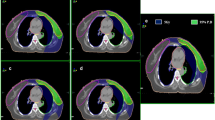

All the patients underwent four-dimensional computed tomography (4D-CT) with Philips Brilliance CT Big Bore simulator in the supine position and free breathing conditions. Patients were scanned using the bellows device placed around the abdomen. Images were binned in 10 phases, with 5-mm thickness throughout the entire neck, thorax, and upper abdomen. The primary lung tumor and lymph nodes measuring ≥ 1 cm in short-axis diameter on thoracic enhanced CT and/or PET positive intake were included in the gross tumor volume (GTV). The internal GTV was contoured on a reconstructed maximum intensity projection image using the 10-phase 4D-CT simulation scan and verified across all phases of the 4D-CT dataset18. The internal clinical target volume (ICTV) was created by expanding the 6–8mm isotropic margin without extending into uninvolved organs. The planning target volume (PTV) was generated by expanding the ICTV by 5 mm isotropically. The TOMO, VMAT, and IMRT treatment plans were performed using Tomotherapy (Accuray Incorporated, Sunnyvale, CA) and Raystation (RaySearch Laboratories AB, Stockholm, Sweden) treatment planning software for each patient. Fixed seven-field and two-arc technique was used in the IMRT and VMAT plans, respectively. A total of 60 Gy in 30 fractions was prescribed to the PTV. The constraints of OARs mainly included as follows: Lung V20 (i.e., percentage of the total lung volume receiving ≥ 20 Gy) ≤ 33%, mean lung dose (MLD) ≤ 17 Gy; mean heart dose (MHD) ≤ 35 Gy, heart V40 ≤ 60%; spinal cord maximum dose ≤ 45 Gy; esophageal maximum dose ≤ 105% of prescription dose. To insure the consistency of all radiation plans, two specially appointed experienced radiation physicians completed and optimized the three different plans of the same patient. All the radiation therapies were performed with linear accelerator 6MV-X. Typical dose distributions for TOMO, VMAT, and IMRT plans of one patient are shown in Fig. 1.

Typical isodose distributions for helical tomotherapy (TOMO), volumetric-modulated arc therapy (VMAT), and intensity-modulated radiotherapy (IMRT) plans for a patient showing the same CT slice. The planning target volume was painted in yellow. The pink, orange, green and red lines represent the dose curves of 5, 20, 30, and 60 (the prescription dose) Gy, respectively.